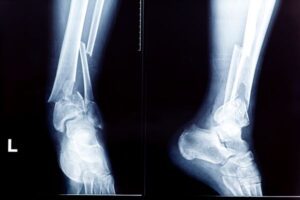

10. Fall safely: If you do fall, try to stretch out your hands to break your fall and avoid fracturing your hip or spine.